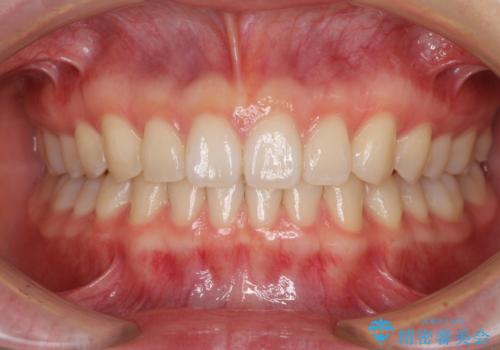

カリエール・ディスタライザーを併用したインビザライン矯正治療

- 上顎前歯の突出感と、前歯のクロスバイトを気にして来院された患者様です。

前歯の叢生と口元の閉じにくさを気にして来院された患者様です。

奥歯の咬み合わせを見ると、上顎が下顎に対して相対的に前方にありました。

カリエール・ディスタライザーを用いたことで上顎前歯の突出感はスムーズに解消され、歯列不正は1年半ほどでほぼ改善することができました。